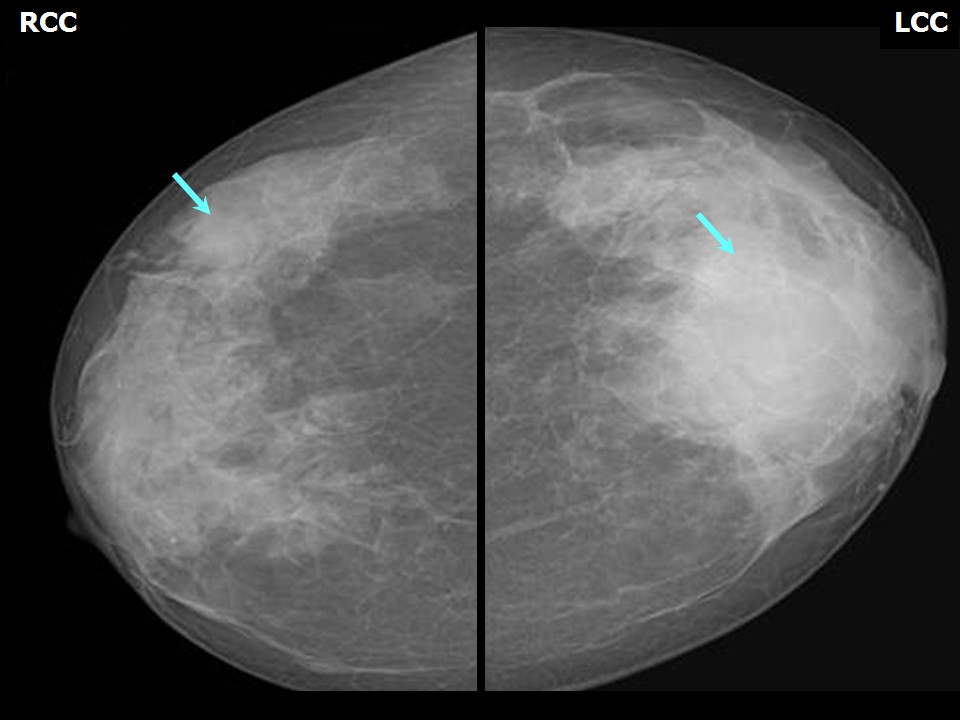

Феномен гипердиагностики в маммографии: примеры и иллюстрации

Раздел: Образы вокруг